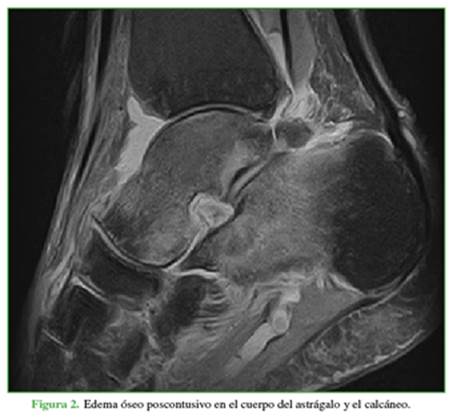

La localización más frecuente del edema óseo fue la cabeza y el cuello del astrágalo (32 pacientes, 64%), comúnmente cuando la RM mostró una lesión lateral o medial (15 casos, 30%). La segunda localización más común fue el cuerpo del astrágalo (20 pacientes, 40%) (Figura 2).

Se observó una lesión del LPC en 27 casos (54%); en el 63%, era parcial y, en el 37%, total. No se detectaron casos de lesión aislada del LPC. En 14 de los casos (52%), la lesión del LPC estaba relacionada con la del LD. Cuando la lesión era doble (LPC más LPAA), el edema óseo apareció en el cuerpo del astrágalo (12 pacientes, 24%) y en la cabeza y el cuello (9 pacientes, 18%). Sin embargo, hubo ocho casos de lesión ligamentaria triple (LPC más LPAA más LD); el edema óseo se detectó, con mucha frecuencia, en el cuerpo del astrágalo, su cabeza o cuello, pero también en el maléolo medial (4 casos) y lateral (2 casos).